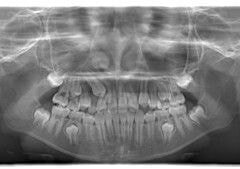

小児期ケース:反対咬合+上顎両側3番埋伏歯

(受け口+右上3番目の永久歯が埋まってしまい、はえてこない)

治療法:上顎急速拡大装置+クリアスナップ+フェイスマスク+上顎右側3番は開窓萌出誘導

(難症例のため、小児期の矯正を2段階にわけました)